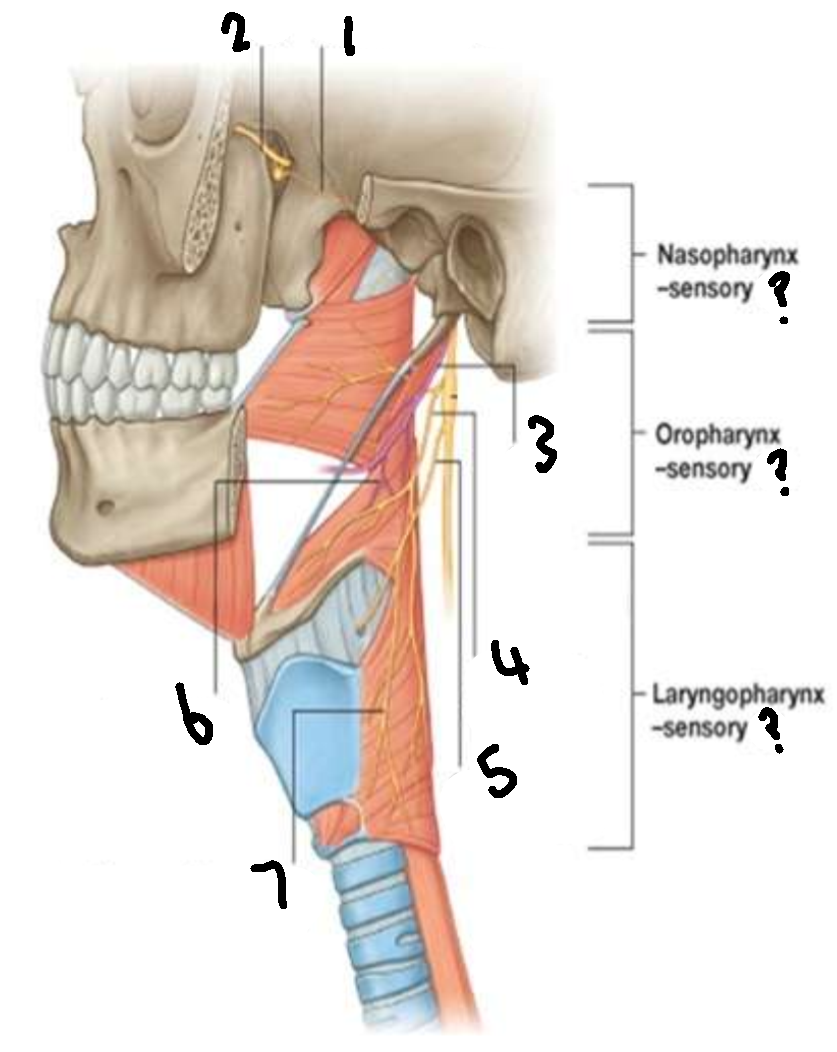

What provides sensory innervation to the nasopharynx?

mandibular branch of trigeminal V2

What provides sensory innervation to the oropharynx?

glossopharyngeal IX

What provides sensory innervation to the laryngopharynx?

vagus X

What is 1?

pharyngeal branch of V2

What is 2?

maxillary branch of trigeminal V2

What is 3?

glossopharyngeal IX

What is 4?

pharyngeal branch of vagus X

What is 5?

superior laryngeal nerve

What is 6?

pharyngeal branch of IX

What is 7?

external laryngeal branch of superior laryngeal nerve of X